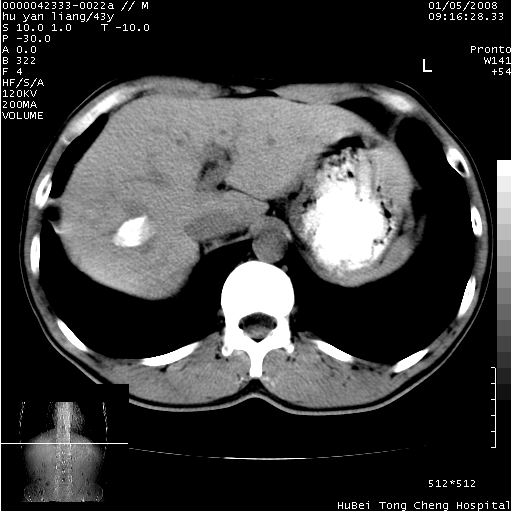

患者 男,43岁。右上腹不适1年余。既往有“肝右叶肝脓肿”病史,经保守治疗后痊愈。

b超提示:1)肝右叶肝内胆管结石。2)肝右叶占位性病变待排。

上中腹部ct轴位平扫+增强扫描(层厚10mm,螺距1.0,重建间隔10mm),图像如下:

肝右上叶偏后方较大团片状钙化灶,支持:肝脓肿后遗改变!

肝右叶后段团块状钙化灶,结合病史考虑肝脓肿痊愈后表现。